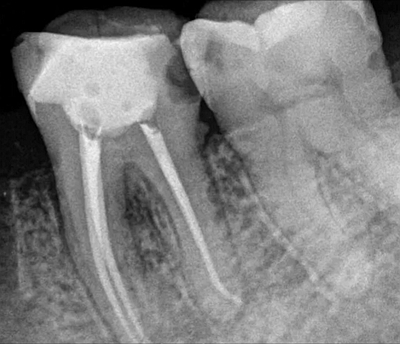

根管充填技術(shù)

1.側(cè)方加壓技術(shù)。充填前按照根管工作長度和所預(yù)備的根管大小,選擇一個合適的主牙膠尖進行充填。

2.垂直加壓技術(shù),將比工作長度短一毫米的主牙膠尖插入根管內(nèi),用熱攜帶器將根管內(nèi)牙膠軟化,垂直加壓直到充填完成。

3.熱塑牙膠充填技術(shù),充填時先將牙膠加熱到所需的溫度,將針頭插入根管至距根尖3~5毫米,先向根尖部擠入少量牙膠,用垂直加壓器壓緊,再繼續(xù)將根管充滿為止。